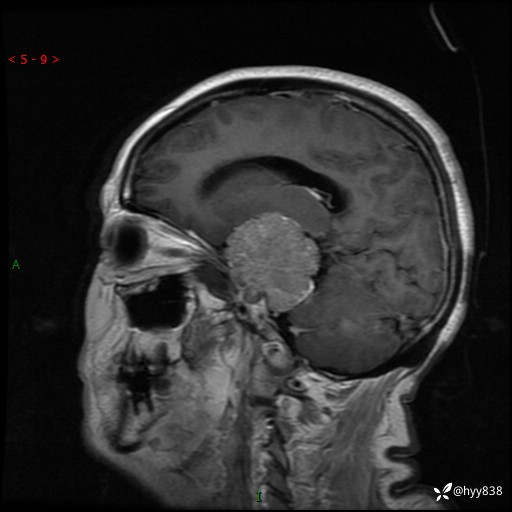

现病史:患者1年前无明显诱因出现双下肢乏力,容易摔倒,无头痛头晕,无肢体抽搐,无口吐白沫,无大小便失禁,无呼吸困难,无发热等不适,2024.08.13-2024.08.16在我院内分泌科住院期间行头MRI(2024.08.15)发现颅内占位,现患者为求诊治来我科,门诊遂以“右侧中颅窝占位性病变”收住院。 起病以来,患者精神饮食睡眠可,大小便正常,体力体重无明显下降。

颅脑MRI平扫+增强